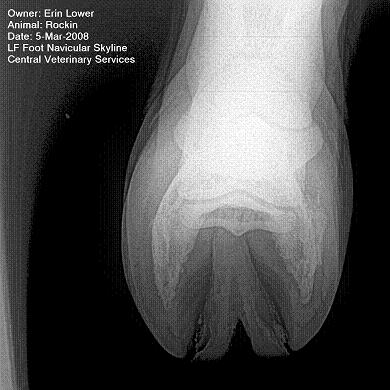

So, Rockin's x-rays were sent to a radiologist and he confirmed "normal" changes in the navicular bones for a horse her age, but slightly more significant ones in the right (sore) foot.

She also has sidebone in both fronts, but apparently that isn't causing any discomfort.

Finally, she has a "small chronic exostosis on the lateral aspect of the proximal phalanx" which, according to the radiologist, shouldn't be causing discomfort but I have read that these can be mild-to-moderately painful... I wouldn't mind another opinion on that.

I will attach as many images as possible from her x-rays (there are many different views). I don't have any pics of the feet as someone deleted them from my camera before I could download them. I'll try to take pics next time she is trimmed. Please, anyone with knowledge of hooves, give any opinions that you might have (especially Dr. O!)

Hello Erin and welcome back,

I cannot rule out lesions based on these images but I will take your radiologist's word that he does not see significant lesions. The exostosis on the RF would be above the level of a well conducted PDN which I believed blocked the lameness before?